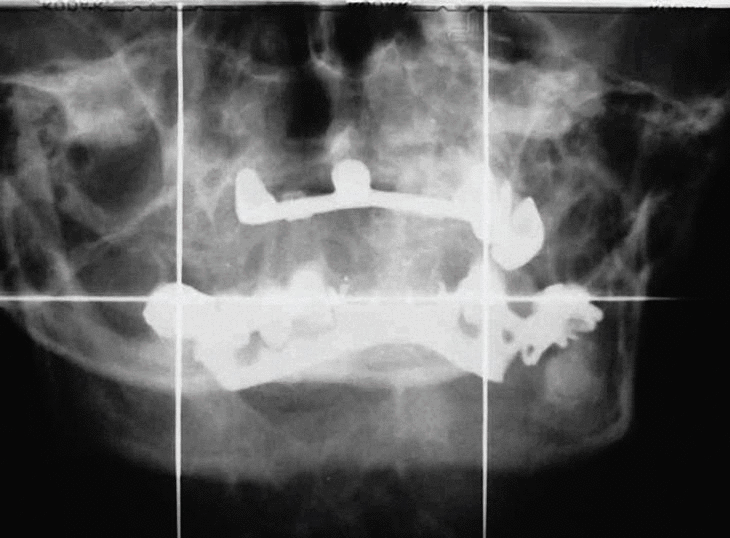

La masticación ha estado dificultada por una mala alineación de la mordida. Después del tratamiento ortodóncico (fig. 3) pudo obtenerse una corrección parcial para que pudiese masticar, aunque los incisivos y caninos no quedaron perfectamente alineados (fig. 4). Las últimas fracturas las sufrió hace 8 años en un accidente de tráfico (fig. 5).

Fig. 3. Corrección de las fracturas maxilares.